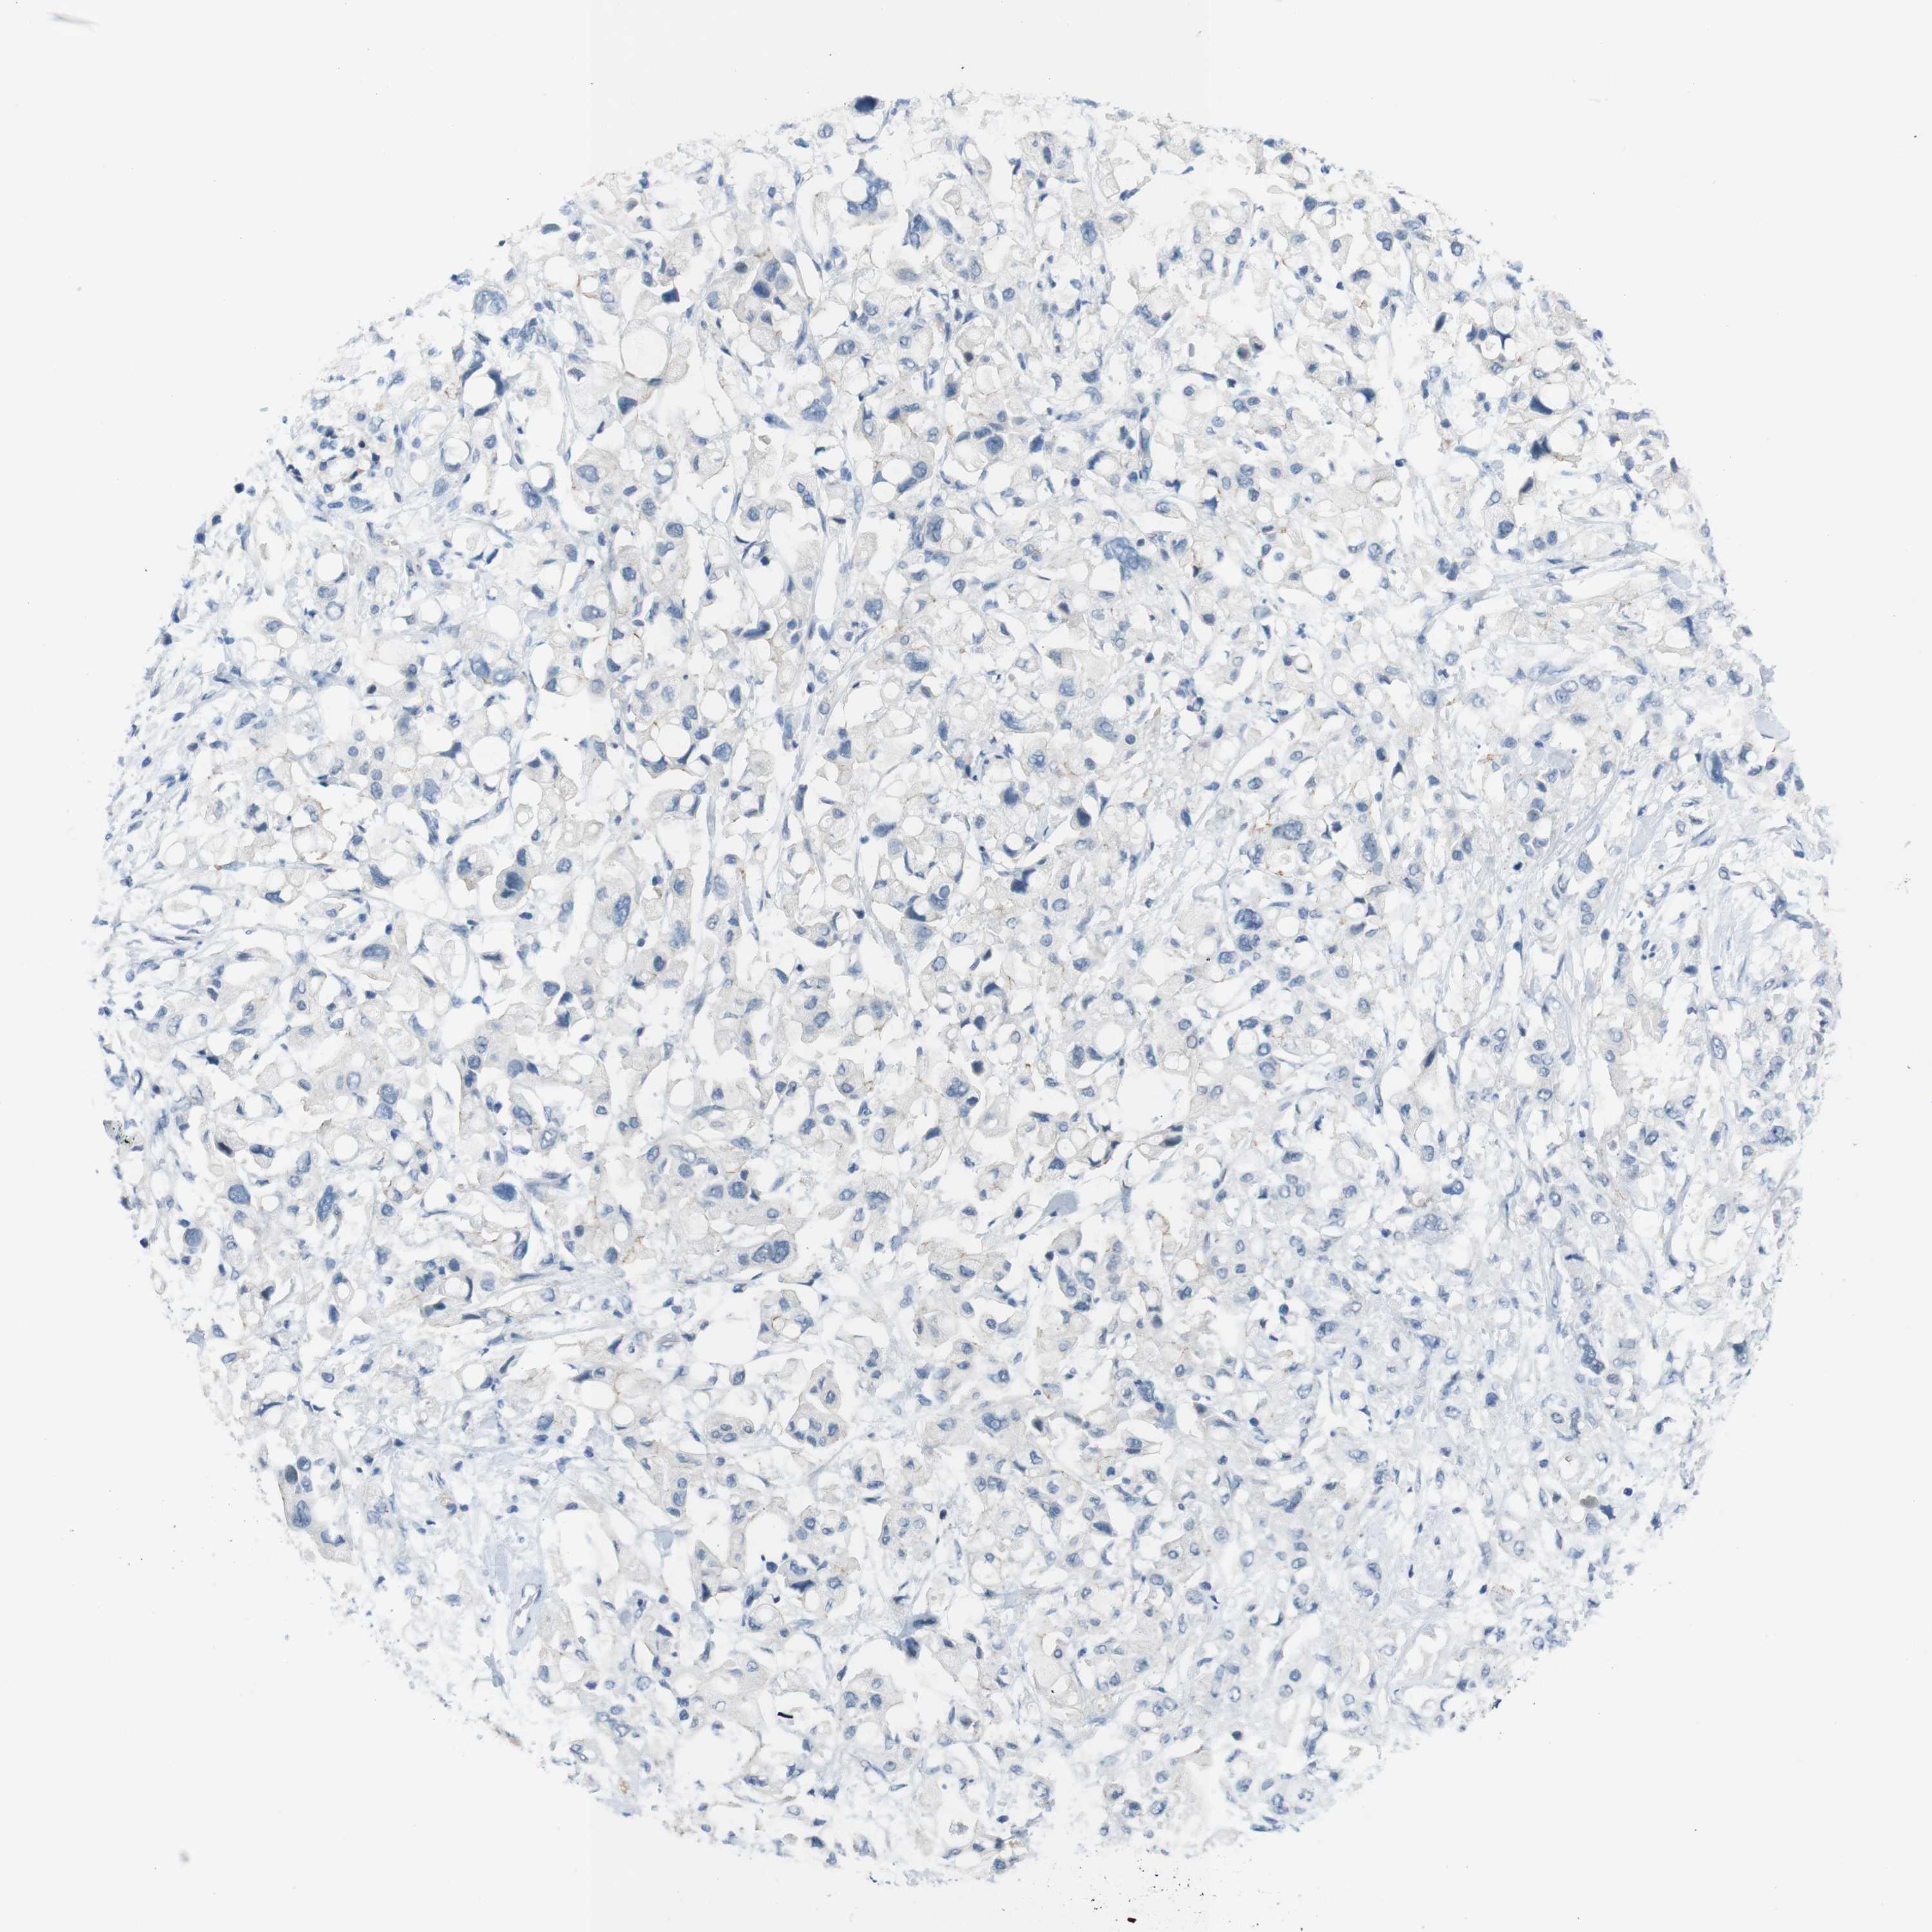

PANCREATIC CANCER - Protein expressioni

A mouse-over function shows sample information and annotation data. Click on an image to view it in a full screen mode. Samples can be filtered based on level of antibody staining by selecting one or several of the following categories: high, medium, low and not detected. The assay and annotation is described here.

Note that samples used for immunohistochemistry by the Human Protein Atlas do not correspond to samples in the TCGA dataset.

Antibody stainingi

Antibody staining in the annotated cell types in the current human tissue is reported as not detected, low, medium, or high, based on conventional immunohistochemistry profiling in selected tissues. This score is based on the combination of the staining intensity and fraction of stained cells.

Each image is clickable and will lead to virtual microscopy that enables deeper exploration of all samples and also displays staining intensity scores, fraction scores and subcellular localization as well as patient and tissue information for each sample.

Antibody HPA013770

Staining

High

Medium

Low

Not detected

Intensity

Strong

Moderate

Weak

Negative

Quantity

>75%

75%-25%

<25%

None

Location

Nuclear

Cytoplasmic/membranous

Cytoplasmic/membranous,nuclear

Adenocarcinoma, NOS

Adenocarcinoma, metastatic, NOS